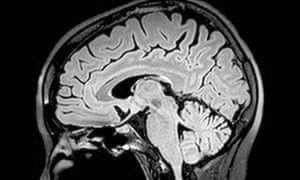

एक स्तर पर हर कोई जानता है कि वह मरने वाला है। इस्राइल के बार इलान विश्वविद्यालय के अध्ययनकर्ताओं की परिकल्पना थी कि जब बात खुद की मृत्यु की आती है तब हमारे मस्तिष्क में ऐसा कुछ है जो “पूर्ण समाप्ति, अंत, शून्यता” जैसे विचारों को समझने से इन्कार करता है।

इस्राइल के एक शोधकर्ता याइर डोर-ज़िडरमन का यह अध्ययन एक ओर मृत्यु के शाश्वत सत्य और मस्तिष्क के सीखने के तरीके के बीच तालमेल बैठाने का एक प्रयास है। उनका मानना है कि हमारा मस्तिष्क ‘पूर्वानुमान करने वाली मशीन’ है जो पुरानी जानकारी का उपयोग करके भविष्य में वैसी ही परिस्थिति में होने वाली घटनाओं का अनुमान लगाता है। यह जीवित रहने के लिए महत्वपूर्ण है। एक सत्य यह है कि एक न एक दिन हम सबको मरना है। तो हमारे मस्तिष्क के पास कोई तरीका होना चाहिए कि वह स्वयं हमारी मृत्यु का अनुमान लगा सके। लेकिन ऐसा होता नहीं है।

इस विषय पर अध्ययन करने के लिए शोधकर्ताओं ने 24 लोगों को चुना और यह समझने की कोशिश की कि स्वयं उनकी मृत्यु के मामले में उनके मस्तिष्क का पूर्वानुमान तंत्र कैसे काम करता है।

ज़िडरमैन और उनकी टीम ने मस्तिष्क के एक विशेष संकेत पर ध्यान दिया जो ‘अचंभे’ का द्योतक होता है। यह संकेत दर्शाता है कि मस्तिष्क पैटर्न को देख रहा है और उनके आधार पर भविष्यवाणी कर रहा है। उदाहरण के लिए, यदि आप किसी व्यक्ति को संतरे के तीन चित्र दिखाते हैं और फिर उसके बाद एक सेब का चित्र दिखाते हैं तब मस्तिष्क में ‘अचंभे’ का संकेत पैदा होता है क्योंकि पूर्व पैटर्न के आधार पर भविष्यवाणी संतरा देखने की थी।

टीम ने वालंटियर्स को चेहरों की तस्वीरें दिखार्इं - या तो उनका अपना या किसी अजनबी का। इन सभी तस्वीरों के साथ कुछ नकारात्मक शब्द या मृत्यु से जुड़े शब्द, जैसे ‘कब्र’ जोड़े गए थे। इसी दौरान मैग्नेटोएनसेफेलोग्राफी की मदद से इन वालंटियर्स की मस्तिष्क की गतिविधियों को मापा गया।

किसी चेहरे को मृत्यु सम्बंधी शब्दों से जोड़ना सीखने के बाद, वालंटियर्स को एक अलग चेहरा दिखाया गया। ऐसा करने पर उनके मस्तिष्क में ‘अचंभा’ संकेत देखा गया। क्योंकि उन्होंने एक विशिष्ट अजनबी चेहरे के साथ मृत्यु की अवधारणा को जोड़ना सीख लिया था, एक नया चेहरा दिखाई देने पर वह आश्चर्यचकित थे।

लेकिन एक दूसरे परीक्षण में वालंटियर्स को मृत्यु शब्द के साथ उनकी अपनी तस्वीर दिखाई गई। इसके बाद जब उनको एक अलग चेहरे की तस्वीर दिखाई गई तब मस्तिष्क ने ‘अचंभा’ संकेत नहीं दिया। यानी जब एक व्यक्ति को खुद की मौत से जोड़ने की बात आई तब उसके भविष्यवाणी तंत्र ने काम करना बंद कर दिया।

दिक्कत यह है कि जैव विकास की प्रक्रिया में चेतना का जन्म हुआ और इसके साथ ही हम समझने लगे कि मृत्यु अवश्यंभावी है। कुछ सिद्धांतकारों के अनुसार, मृत्यु के बारे में जागरूकता से प्रजनन की संभावना कम हो सकती है क्योंकि आप मौत से डरकर जीवन साथी चुनने के लिए आवश्यक जोखिम नहीं उठाएंगे। एक परिकल्पना है कि दिमाग के विकास के साथ मौत जैसी वास्तविकता से इन्कार करने की क्षमता विकसित होना अनिवार्य था। अध्ययन के निष्कर्ष जल्द ही न्यूरोइमेज जर्नल में प्रकाशित किए जाएंगे। (स्रोत फीचर्स)